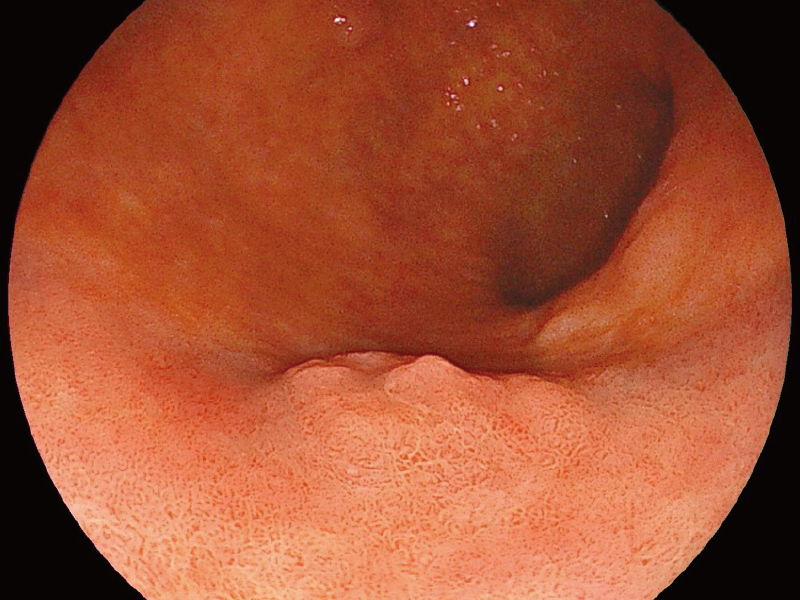

The down-angulation of EG-840T and EG-840TP increased to 160° from 90° while maintaining an up-angulation of 210° which can be found on all 700 series gastroscopes. It is expected to facilitate the observation and treatment of lesions and sites that have been difficult to approach in the past.

The 2mm close-up observation is expected to improve visibility during treatment.

*3

White Light Imaging

*3 The images are not strictly close observation at 2 mm